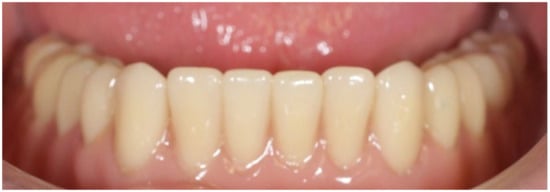

2. Materials and Methods

3. Results